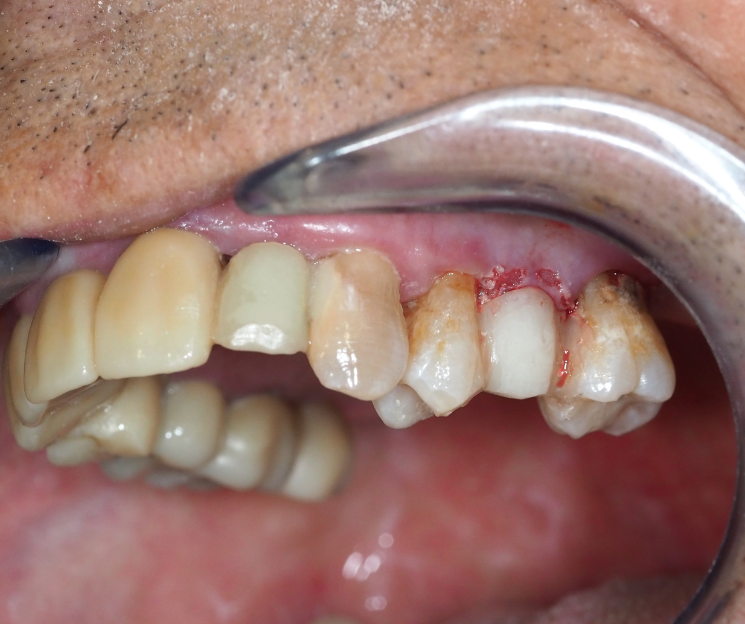

Rehabilitación Inmediata

Manteniendo la función y la estética:

Una de las máximas de nuestra filosofía de tratamiento es no dejar nunca al paciente sin dientes. Por ello, tras la cirugía, se colocó una rehabilitación provisional que permitió al paciente:

- Mantener la estética en la zona anterior/posterior.

- Conservar la función masticatoria durante el periodo de osteointegración.

- Evitar el periodo de espera desdentado.

Se realizará un seguimiento hasta la colocación de la corona definitiva de circonio tras la regularización de los tejidos blandos.